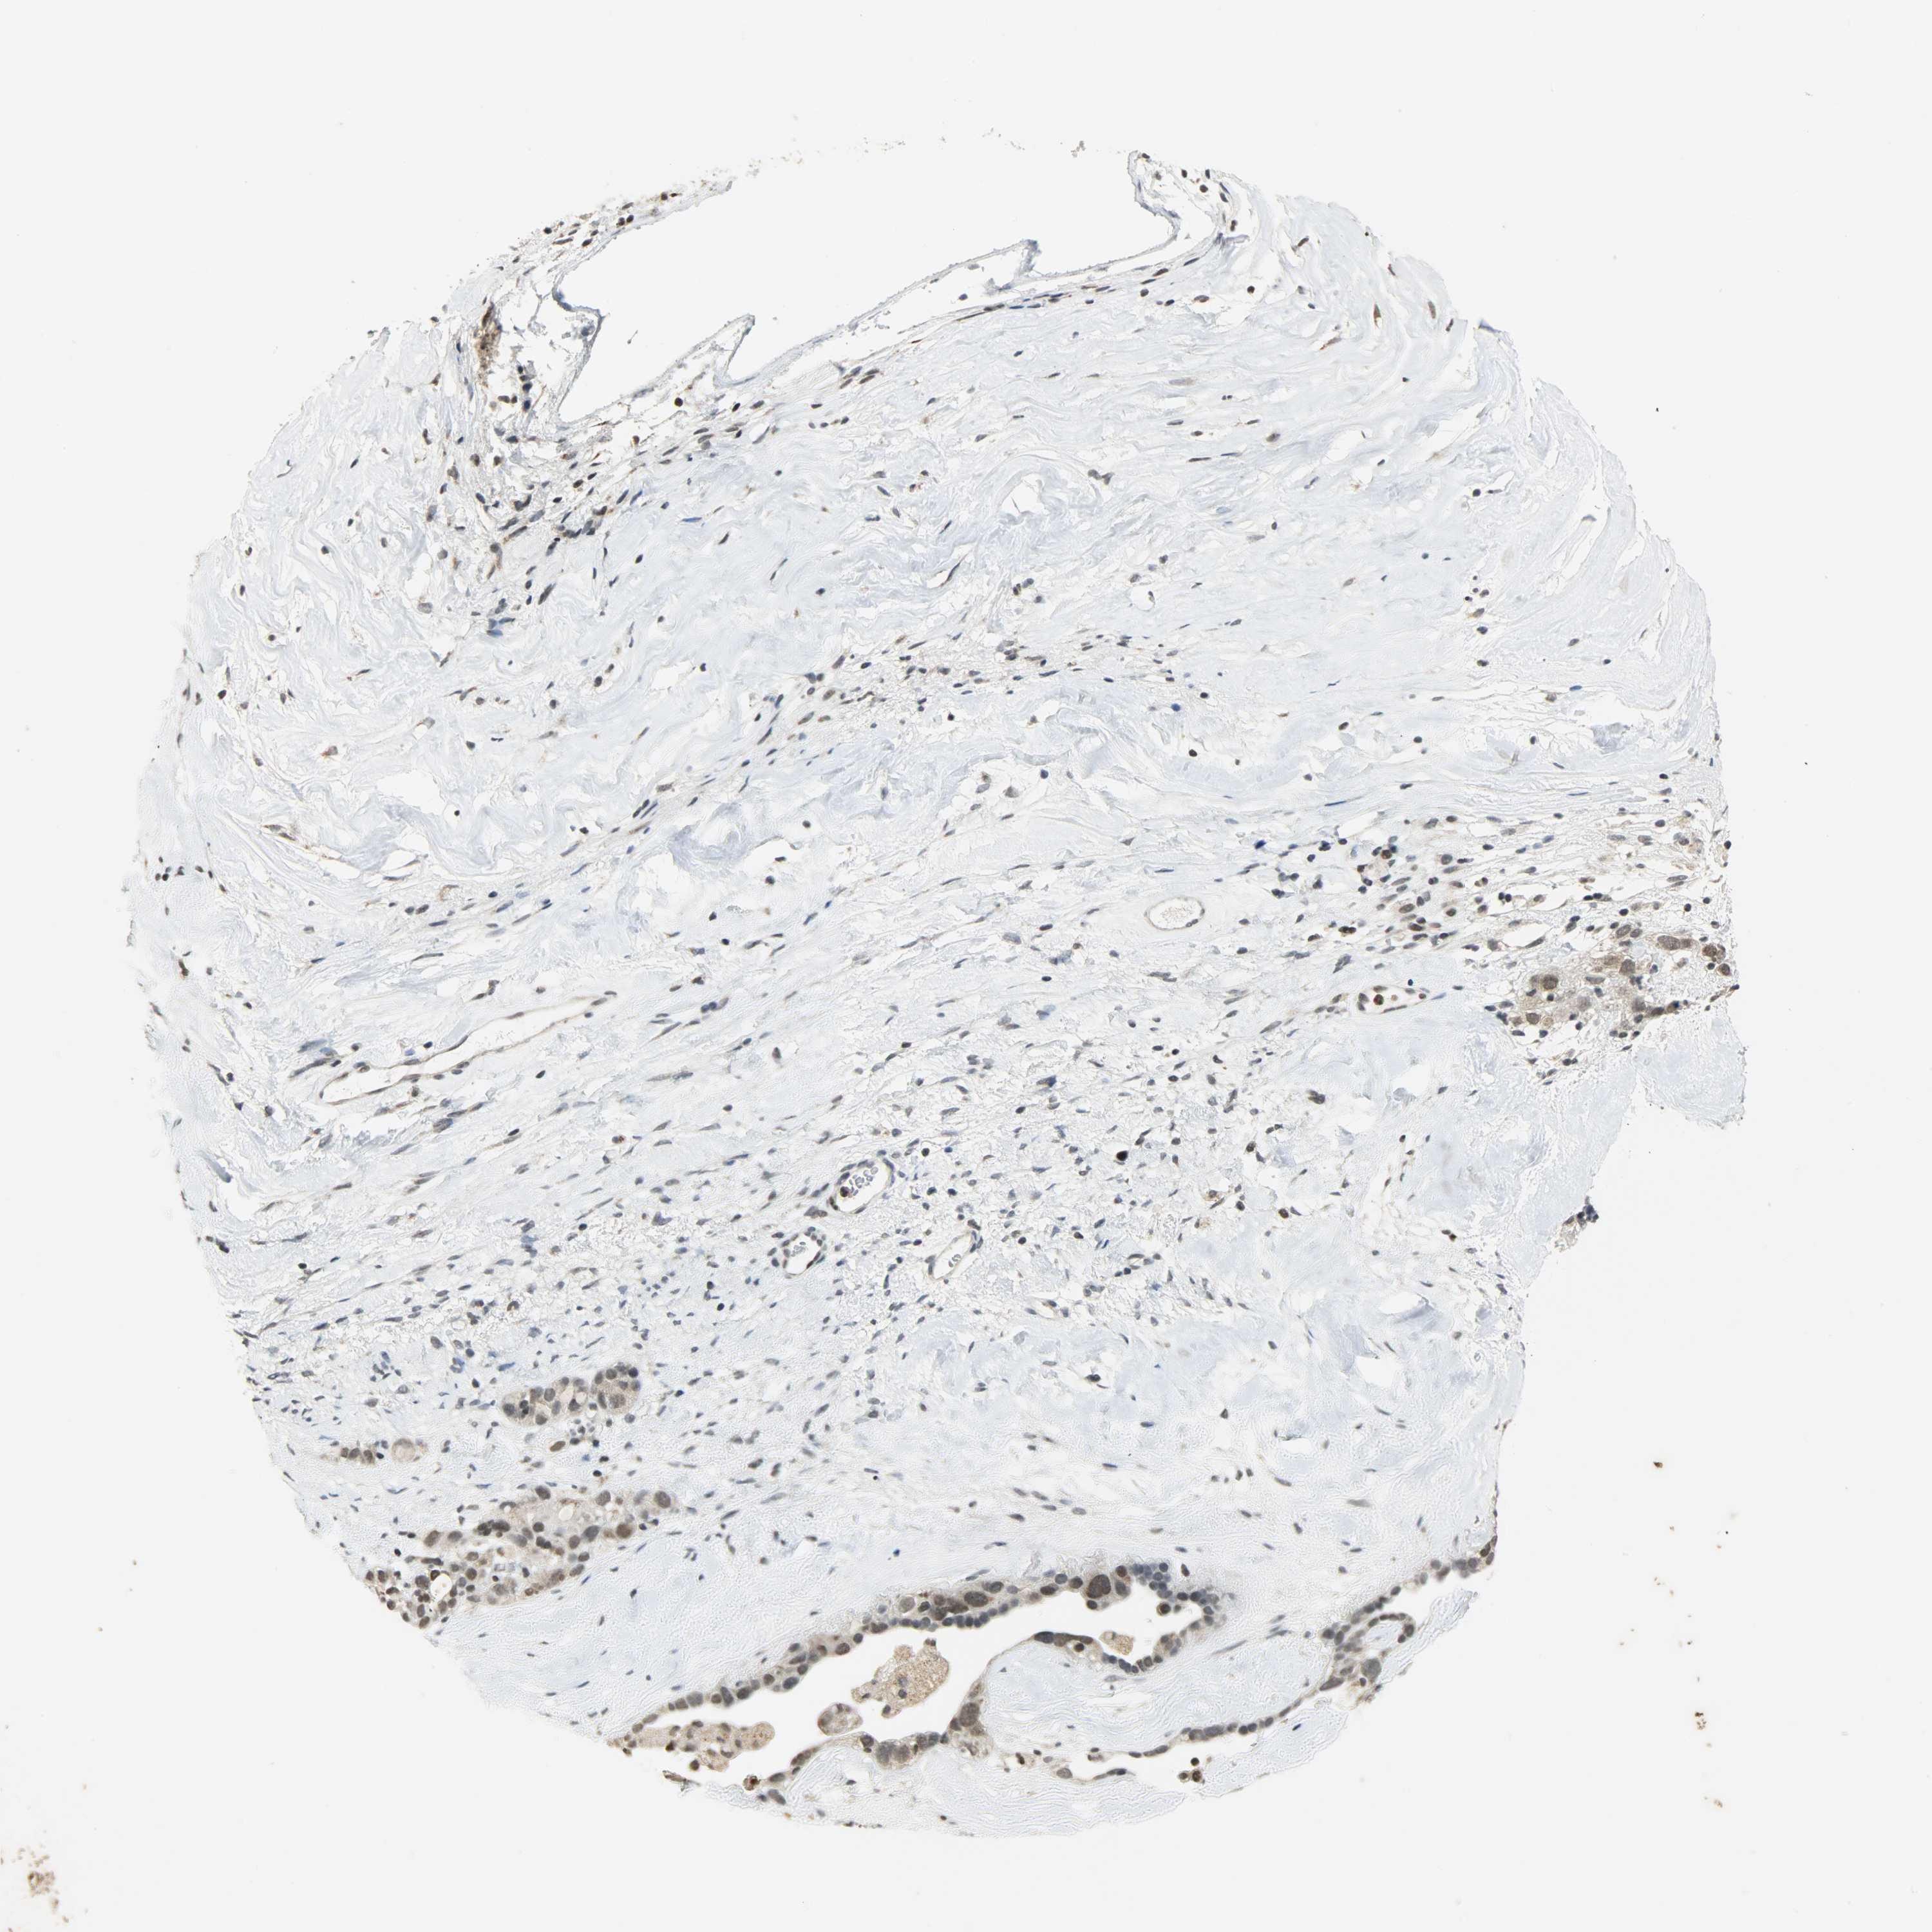

OVARIAN CANCER - Protein expressioni

A mouse-over function shows sample information and annotation data. Click on an image to view it in a full screen mode. Samples can be filtered based on level of antibody staining by selecting one or several of the following categories: high, medium, low and not detected. The assay and annotation is described here.

Note that samples used for immunohistochemistry by the Human Protein Atlas do not correspond to samples in the TCGA dataset.

Antibody stainingi

Antibody staining in the annotated cell types in the current human tissue is reported as not detected, low, medium, or high, based on conventional immunohistochemistry profiling in selected tissues. This score is based on the combination of the staining intensity and fraction of stained cells.

Each image is clickable and will lead to virtual microscopy that enables deeper exploration of all samples and also displays staining intensity scores, fraction scores and subcellular localization as well as patient and tissue information for each sample.

Antibody HPA008751

Antibody CAB005227

Cystadenocarcinoma, mucinous, NOS